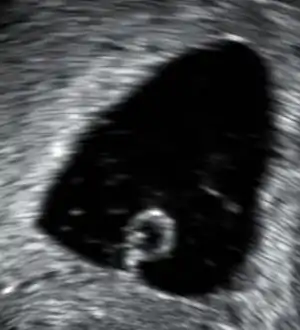

| An ultrasound showing a gestational sac containing a yolk sac but no embryo. | |